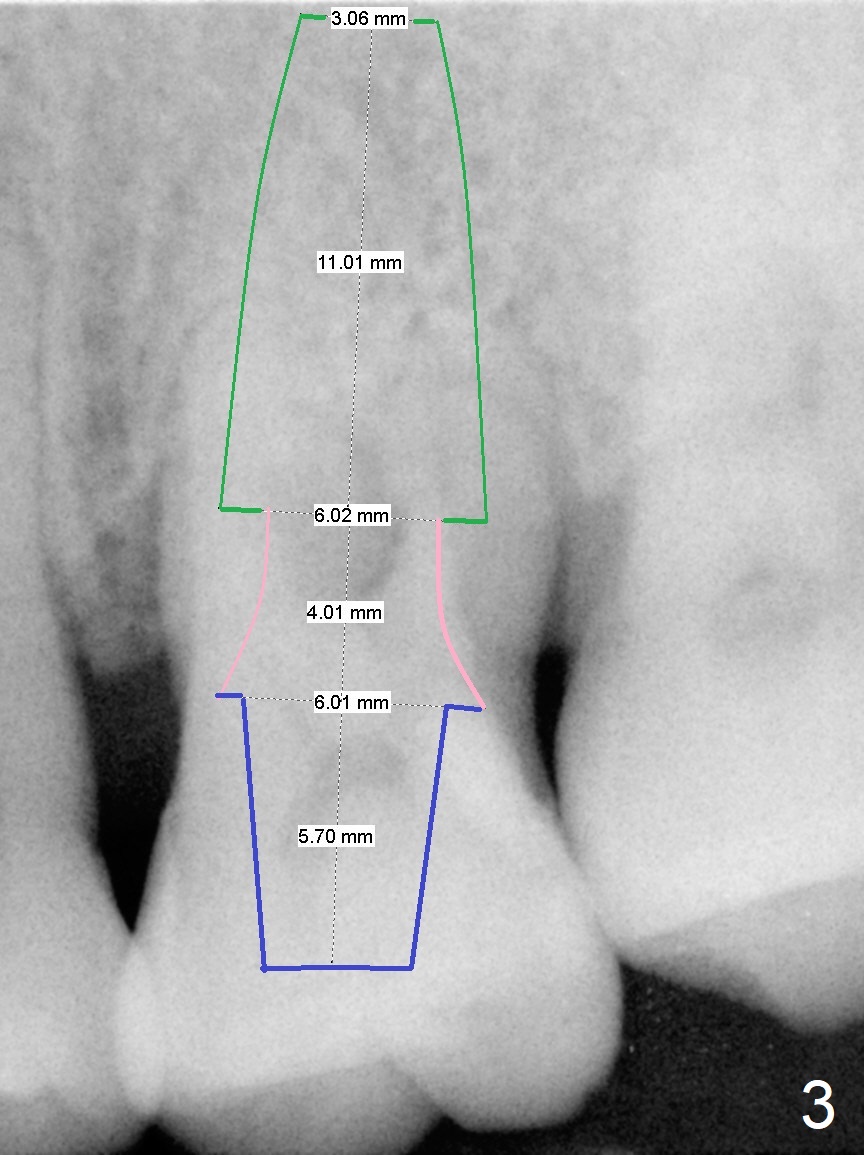

A 44-year-old man is a typical patient with chronic periodontitis (Fig.1). Periimplantitis develops following immediate implant at #31 (Fig.2). The symptom (bleeding) improves after bone graft and use of Water Pik. Now the tooth #14 appears to be non-salvageable because of gingival hemorrhage and deep pockets after previous osseous surgery. To prevent periimplantitis, an immediate implant does not need to be large or long. It has to be placed deep, and in the middle of the native bone, surrounded by bone graft. To facilitate wound healing, draw 3 tubes of blood for PRF. One of them is processed for plug in case of sinus lift. To prevent the buccal gingiva collapse, the buccal portion of the immediate provisional should extend into the socket. If the gingiva is around 4 mm, use IBS implant (Fig.3,4). Otherwise, a SM implant will be used after extraction (Clindamycin), since abutments have cuffs as long as 4.5 and 6 mm so that it is easy to place an implant as deep as possible. Initial depth will be 9 mm (bone-level), followed by Magic Drill (5.3 mm, if possible) and Magic expanders (4.3x10 and 4.8x11 mm, bone density 26-300 units).